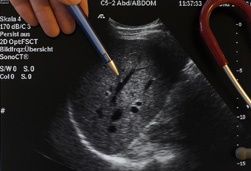

Diagnose Fettleber oder ist die Fettleber eine Zivilisationskrankheit?

In den Industriestaaten kann eine Fettleber bei nahezu jedem Dritten gefunden werden. Meist ist sie nur ein Zufallsbefund, z.B. im Rahmen einer Ultraschalluntersuchung (Sonographie). Aber immer häufiger werden Fettlebern im Rahmen der Abklärung krankhafter Leberwerte gefunden. Ca. 2...